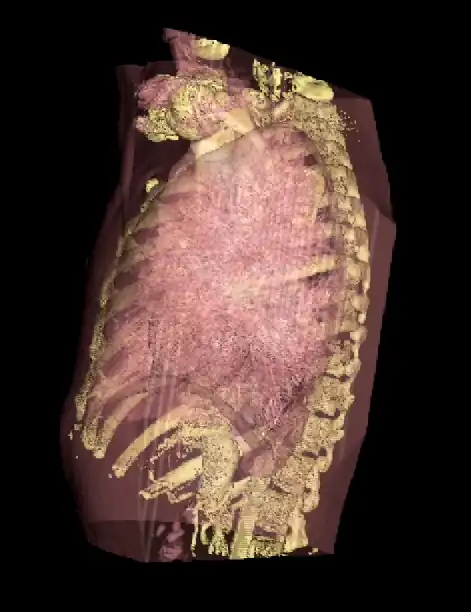

Notice that internal features of each lung can be discerned when the opacity is reduced. Notice also that continued viewing of this type of transparency display can generate apparent reversal of the image rotation, similar to that noted for the 3D MIPs above. One method of overcoming this type of problem is to segment each lung, for instance. and to blend the results, as illustrated in the following figure:

subFusion Processing

We'll conclude this chapter by considering an application of 3D visualization which integrates many of the image processing techniques we've described in this wikibook. We'll use the two SPECT scans, from a patient's lung-ventilation (V) and lung-perfusion (Q) studies, in an attempt to visualize any mismatch(es) characteristic of pulmonary embolism (PE). The application we'll consider is called subFusion Processing because it involves both image subtraction and image fusion techniques.

Note again that the SPECT studies were generated using a swamping technique where the perfusion scan was acquired immediately following the ventilation scan using an administered activity which generated a relative count rate of about 5:1 between scans. The first image processing step therefore is to correct the perfusion scan for the background ventilation activity.

Since the ventilation tracer in this case was administered using a aerosol, we can assume for simplicity that its biodistribution is reasonably identical in the two scans. Further, since the scans were acquired about 15 minutes apart using the 99mTc radioisotope, we can assume a negligible effect from radioactive decay. We can simply therefore subtract the ventilation stack from the perfusion stack, on the basis of these assumptions, to isolate what we'll call the "pure perfusion" scan.

The second step is to normalize the two scans by multiplying the ventilation stack by a factor such that the mean counts (for example) in the two stacks are similar.

- We can now compare apples with apples!

Since a PE mismatch is likely to arise from regions of the lungs which contain counts in the ventilation scan and are relatively bereft of such counts in the perfusion scan, we can subtract the "pure perfusion" stack from the ventilation stack, as a third image processing step, to isolate any such differences as positively-valued features.

The final image processing step is to volume render this difference stack along with the "pure perfusion" scan and to blend the results, as illustrated in the following image:

The steps involved are outlined in the following diagram. Note that minor processes, such as CLUT selection, relative opacity adjustment and contrast enhancement are omitted from this diagram for the sake of simplicity. Note also that an image registration step may need inclusion at the beginning of the procedure in cases where patient movement occurs between the two SPECT acquisitions.

A final point to note is the larger appearance of the patient's lungs in the segmented CTPA images relative to the SPECT images. This arises because the CTPA study was acquired using a single breath-hold and the SPECT studies with the patient breathing quietly over the period of gamma camera rotation. The spatial registration of the three sets of images is therefore not possible directly, and would require the application of spatial warping and other techniques which, unfortunately, are beyond the scope of our treatment here.